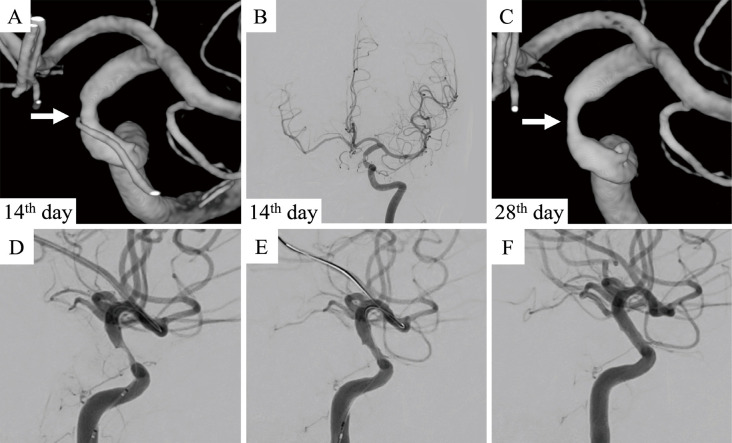

We report a case of invasive sphenoid sinus aspergillosis with progressive internal carotid artery (ICA) stenosis and contralateral carotid occlusion that was successfully treated with percutaneous transluminal angioplasty and stenting (PTAS). A 70-year-old man presented with right-sided visual disturbance, ptosis, and left hemiparesis. Magnetic resonance imaging of the head revealed a space-occupying lesion within the sphenoid sinus with infiltration of the bilateral cavernous sinuses, right ICA occlusion, and multiple watershed cerebral infarcts involving the right cerebral hemisphere. The patient was diagnosed with invasive sinus aspergillosis based on transnasal biopsy findings. Despite intensive antifungal therapy using voriconazole, rapidly progressive aspergillosis led to a new stenotic lesion in the left ICA, which increased the risk of bilateral cerebral hypoperfusion. We performed successful PTAS to prevent critical ischemic events. Finally, aspergillosis was controlled with voriconazole treatment, and the patient was discharged. He showed a favorable outcome, with a patent left ICA observed at a 3-year follow-up. PTAS may be feasible in patients with ICA stenosis and invasive sinus aspergillosis.